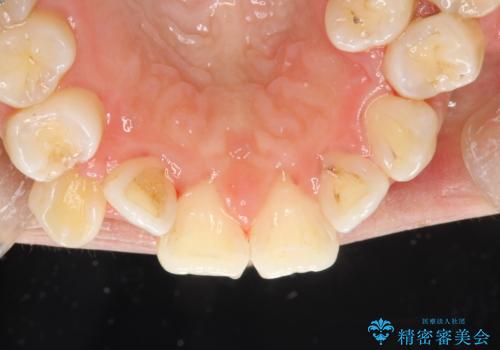

プラーク(細菌の塊)や歯石がたまると歯の表面はザラつきいてきます。そのザラつきは歯周病や虫歯菌の棲家となります。そのまま放置すると、歯肉が腫れてきたり、歯肉から出血したり、口臭が強くでたりします。とくに歯肉の境目は、歯磨きで汚れを除去することが難しく、プラーク(細菌の塊)や歯石が溜まりやすい場所です。

歯並が、がたついている場合はなおさら汚れが溜まりやすいです。矯正治療前や定期的にPMTCをすることで、矯正治療中の歯肉トラブルを防ぐことにつながります。